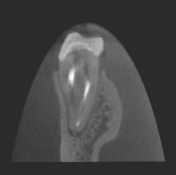

70μm(Voxel Size)高精細モード搭載

End、根尖、破析、分岐部病変など精細読影をサポートします。

CT撮影時、Free FOVで撮影に必要な領域を絞り込み、

的確に高解像度70μmの世界トップレベルのCT画像を再現します。-

前歯クラック

(亀裂) -